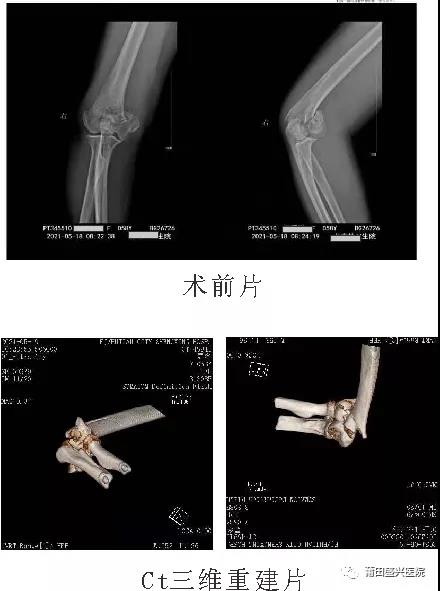

日前,有一女性患者王xx,右肱骨髁間粉碎性骨折,經(jīng)過(guò)與家屬及本人溝通后,我院業(yè)務(wù)副院長(cháng)……